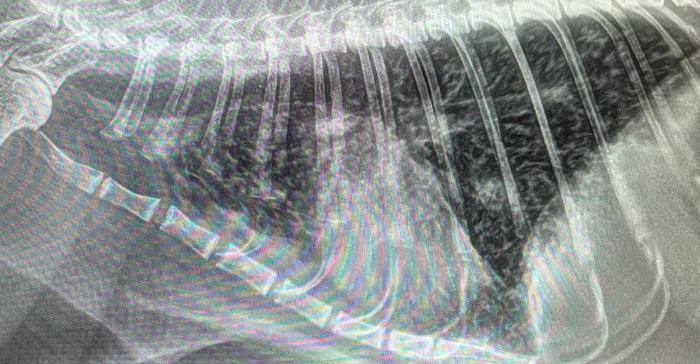

Я делаю рентген на приёме и видим такое:

Правая латеральная поверхность

Мы видим классическую картину многодолевой пневмонии - будто профилактика на канале ночью. Прямая проекция выглядит так же, поражены все доли обоих лёгких.

Снимок через 14 дней после АБ. Воздушность усилилась, отёчность тканей подспала и теперь мы видим те самые нодулярные узлы и на рентгене.